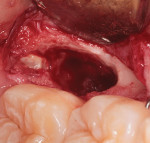

An oral surgeon reviewed the case and recommended an incisional biopsy, which was completed under local anesthesia. Using a small mucoperiosteal envelope flap for access, crestal bone was removed and sufficient lesional tissue was obtained for histological analysis. The lesion was histologically determined to be comprised of a fibrous connective tissue wall lined by a non-keratinized stratified squamous epithelium, containing acute and chronic inflammatory infiltrate (Figure 5). Based on the combined clinical, histological, and radiographic findings, and considering the anatomical site, a diagnosis of BBC was made with the recommendation for the complete surgical enucleation of the cyst. This was subsequently completed (Figure 6 through Figure 8), and an allogeneic bone graft was placed into the defect. Postoperative healing was evaluated at a 2-week interval with no complications.